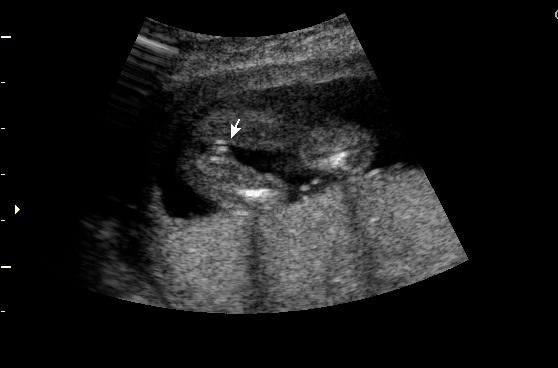

Attached is my 16 week 3 day scan. 11 week 3 day nub indicated girl - obviously very early so not reliable. Looking for second opinions on the sex of the baby! Thank you. :)

Definitely a girly 'hamburger' - congrats!

3 lines = girl!!! Congratulations!!!